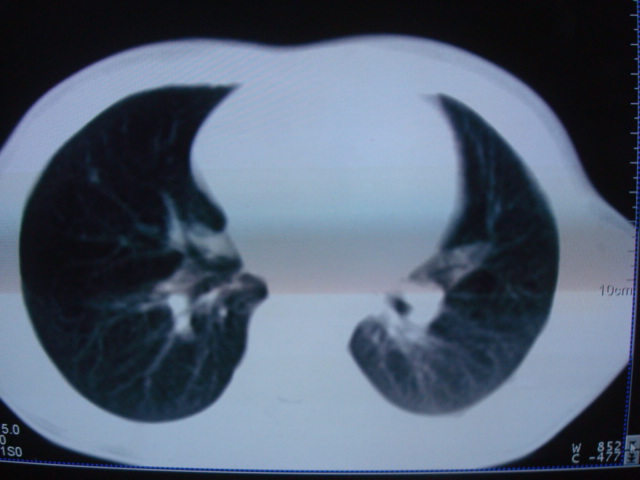

标题: PED0869:男,10岁,肺内多发结节+胸水

男,10岁,左胸痛,发热轻,血象高。后到省级权威医院治疗,病情明显好转,结果几天后公布。老机器,图像质量差,见谅。